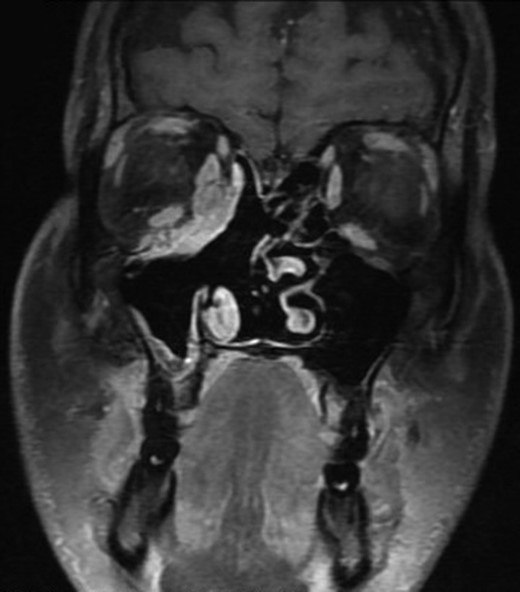

Subsequently, molecular study using fluorescence in situ hybridization (FISH) had shown rearrangement of EWSR1 gene in 100% of the analyzes nuclei that confirm the diagnosis of Ewing’s sarcoma. The patient underwent endoscopic excision of the tumor followed by chemotherapy and radiotherapy treatment. MRI 6-months post treatment showed complete resolution of the disease (Fig. 5). The patient remains symptom-free during 2 years follow-up and maintains a very good quality of life.

Magnetic resonance imaging after treatment. MRI post treatment showing total resolution of the tumor.